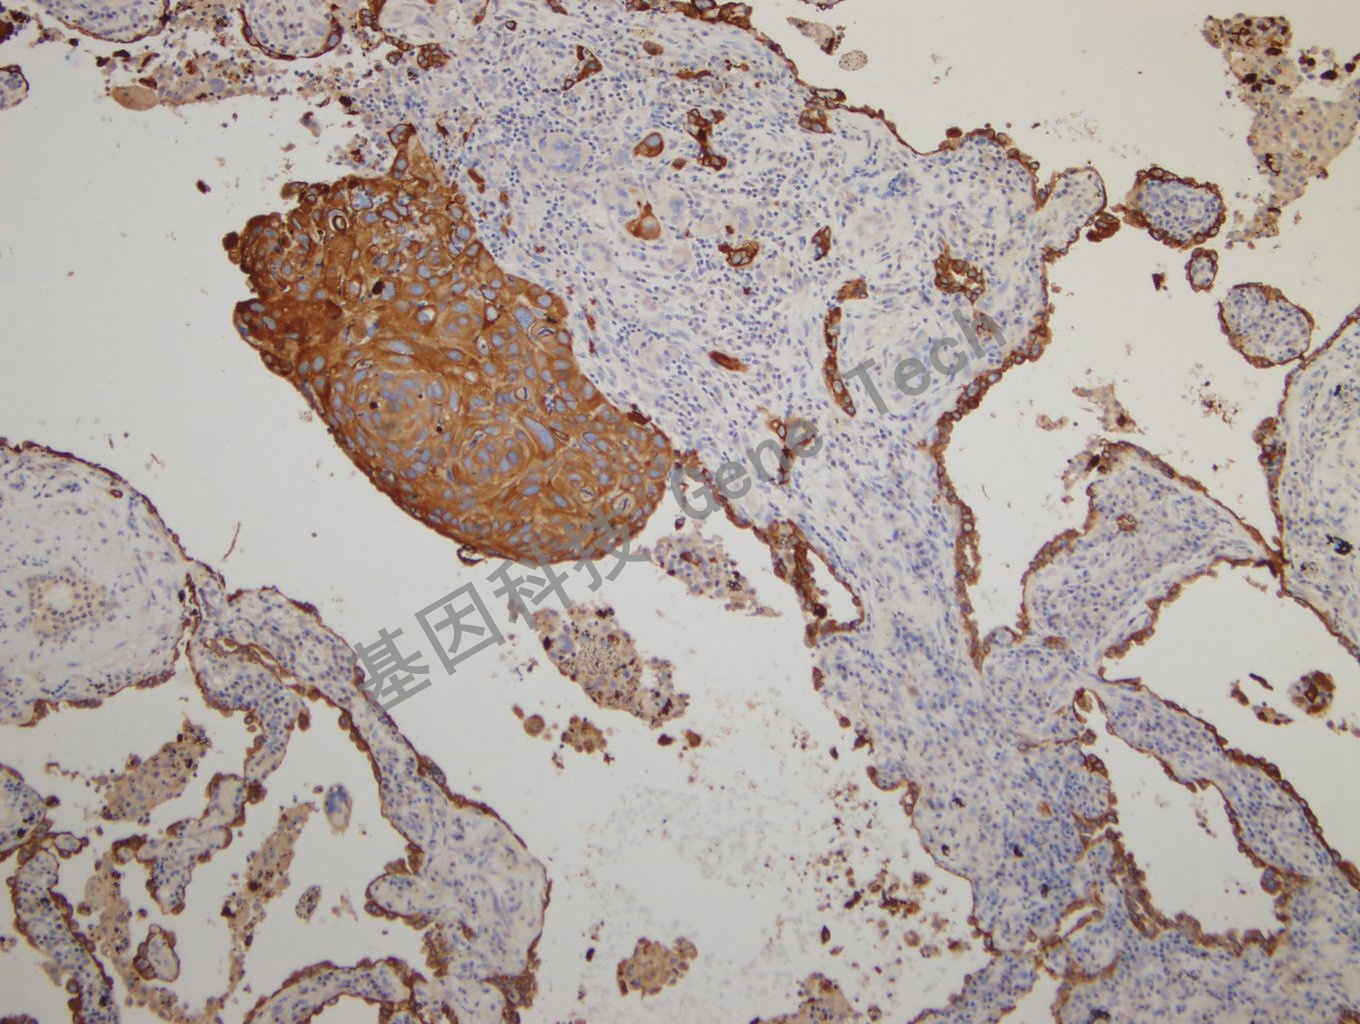

肺鳞癌石蜡切片,用 CK,pan(GM3515)染色,细胞浆阳性,DAB 显色。